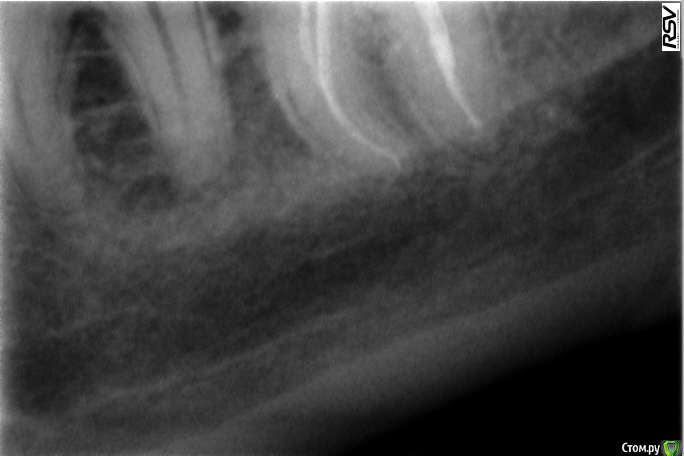

katrineigma Опубликовано 10 октября, 2015 Поделиться Опубликовано 10 октября, 2015 (изменено) Добрый день.Мне депульпировали зуб, дней через 5 после этого он начал просто невыносимо болеть, врач сказал, что зуб запломбирован хорошо, немного выведен пломбировочный материал за верхушку корня, но это не страшно, просто постпломбировочные боли. Дней 10 жила на обезболивающих, потом болеть все перестало. Сейчас прошло 4 месяца с того момента, зуб стал периодически ныть, сделала рентген в другой клинике - воспаление. Врач этой клиники говорит, что вряд ли такое воспаление может быть из-за выведенного за пределы корня материала, и вообще его не так много выведено, скорее всего, когда делали зуб, не нашли просто еще один канал и он остался пустым, от того и воспаление. Очень хотелось бы услышать мнения, в чем реальная причина воспаления всё-таки, и рекомендации, что теперь делать с зубом, можно ли его перелечить и нужно ли, или лучше не трогать? Прикладываю 2 снимка сразу после пломбировки каналов и 1 свежий, с воспалением.Заранее спасибо. Изменено 10 октября, 2015 пользователем katrineigma Ссылка на комментарий

Shaid Опубликовано 11 октября, 2015 Поделиться Опубликовано 11 октября, 2015 Дело в инфекции, которая находится в корневом канале - в запломбированном или не найденном пустом канале. 1 Ссылка на комментарий